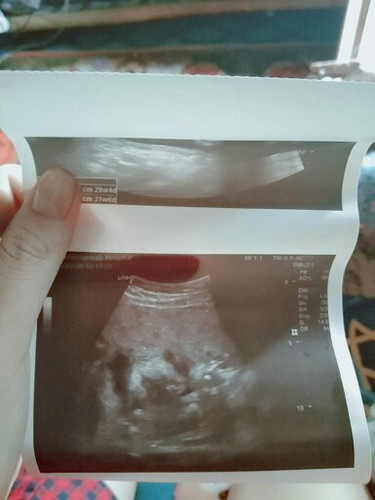

อัลตร้าซาวด์มา เอารูปมาฝากคุนเเม่ ท้อง7เดือน กำหนดคลอดเดือนเมษาๆ น้ำหนัก1900น้อยไปไม่ เเต่หมอบอกว่าไมเปงไรๆ น้ำหนักยุในเกณฑ ลูกตัวใหญ กัวลงเเม่มากเเต่หมอบอกว่าลงลูก ทุกคนก้พูดว่าลงเเม่ รุ้สึกน้อยนิดๆๆ

เทียบกับในแอพสิค่ะ เราว่าใหญ่มากเกินเกณฑ์ด้วยนะแม่